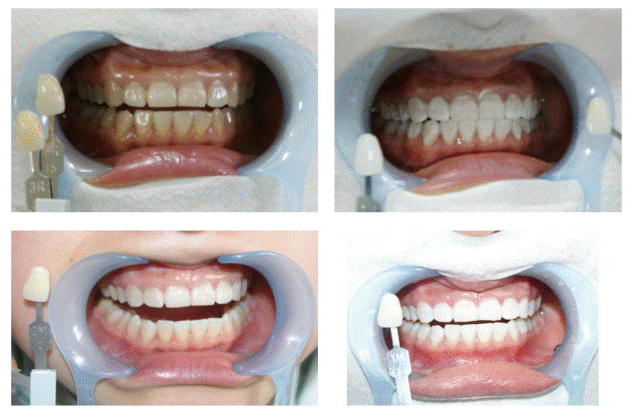

“无痛、微创、舒适是科室牙科治疗的三大理念,如何实现呢?”

A4随着牙科设备、技术、材料的飞速发展,无痛、微创的舒适治牙理念逐渐深入人心。科室在湖南率先推行笑气镇痛镇静下治牙,使口腔疾病的患者能在无痛状态下接受口腔治疗,该方法的应用受到患者的交口称赞。我科拥有的计算机控制无痛口腔麻醉仪、笑气镇静镇痛仪、顶级根管手术显微镜、Fotona激光、Er,Cr:YSGG激光,和专业的显微牙医是无痛微创舒适治疗的保证。患者在享受高科技设备的同时,还有科室医护人员温馨体贴的四手操作,最大限度地降低了患者对看牙的恐惧!